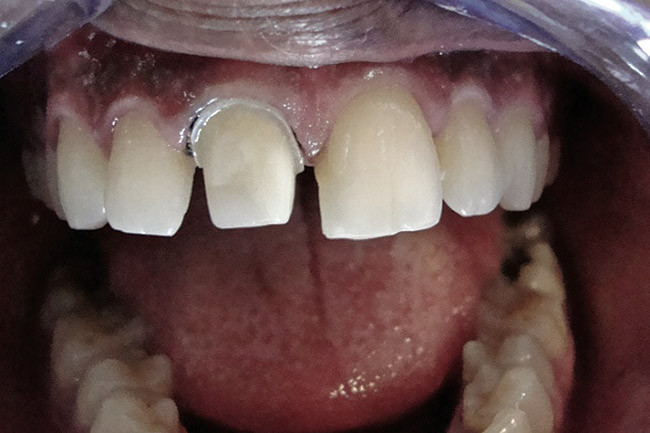

Figure 2  Caries extending cervically on upper right incisors.

Figure 2

Figure 3  Placement of rubber dam with application of cervical clamp on central incisor for extra retraction.

Figure 3